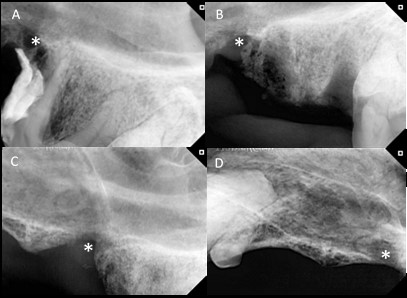

Figura 4:  Radiografías correspondientes al caso 2. A: En la radiografía se visualizan restos de resina radiopacos sobre las raíces mesiales de la pieza 208 y pérdida ósea adyacente a los restos de resina (*). A su vez presenta disminución de la radiodensidad ósea del hueso alveolar entre las raíces mesiales y la distal. También se observa una discontinuidad en la tabla ósea compatible con fístula oronasal. B: Radiografía inmediata a la exodoncia de la pieza 208 y extracción de la resina. Se visualizan los espacios correspondientes a los alvéolos dentales vacíos y la rarefacción ósea con disminución de radiodensidad craneal a los alvéolos dentales compatible con osteomielitis (*). C: Radiografía correspondiente a la zona de la pieza 208, 3 meses luego de realizada la exodoncia y colocación de PRF, se observa una remodelación ósea con aumento de la radiodensidad ósea en la zona correspondiente al alvéolo de las raíces mesiales y en la zona correspondiente al defecto óseo generado por la resina (*). D: Radiografía a los 9 meses de la exodoncia y aplicación de PRF. Presenta una buena radiodensidad a nivel óseo en la zona correspondiente al defecto (*). Tomada del Servicio de Odontoestomatología de la Facultad de Veterinaria, Udelar.